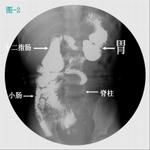

3、X線檢查:X線是診斷本病的重要手段之一,腹部平片可見結腸充氣擴張,在腹外圍呈連續空柱狀透亮區,小腸也有脹氣,但無大的液平面可與小腸梗阻鑑別。直腸壺腹無氣體也是重要區別點。有人建議做倒置位正側位腹部、盆腔攝片,如氣體不能升人直腸,診斷就更可靠。

4、鋇劑灌腸X線拍片對診斷病變在直腸、乙狀結腸的病例,準確率達90%以上。病變部位可見直腸持續性狹窄,呈漏斗狀與擴張的腸段相接,動態像顯示結腸蠕動強烈而規則,排鋇後由於腸壁和黏膜增厚,見腸腔內有明顯皺褶,類似正常空腸皺褶,被稱為所謂的“結腸空腸化”改變。多數患兒不能及時排鋇,觀察排鋇功能是對新生兒巨結腸的重要診斷。並髮結腸炎時,X線可見近端擴張結腸的輪廓模糊,外形僵直,有多數不規則的毛刺突出。